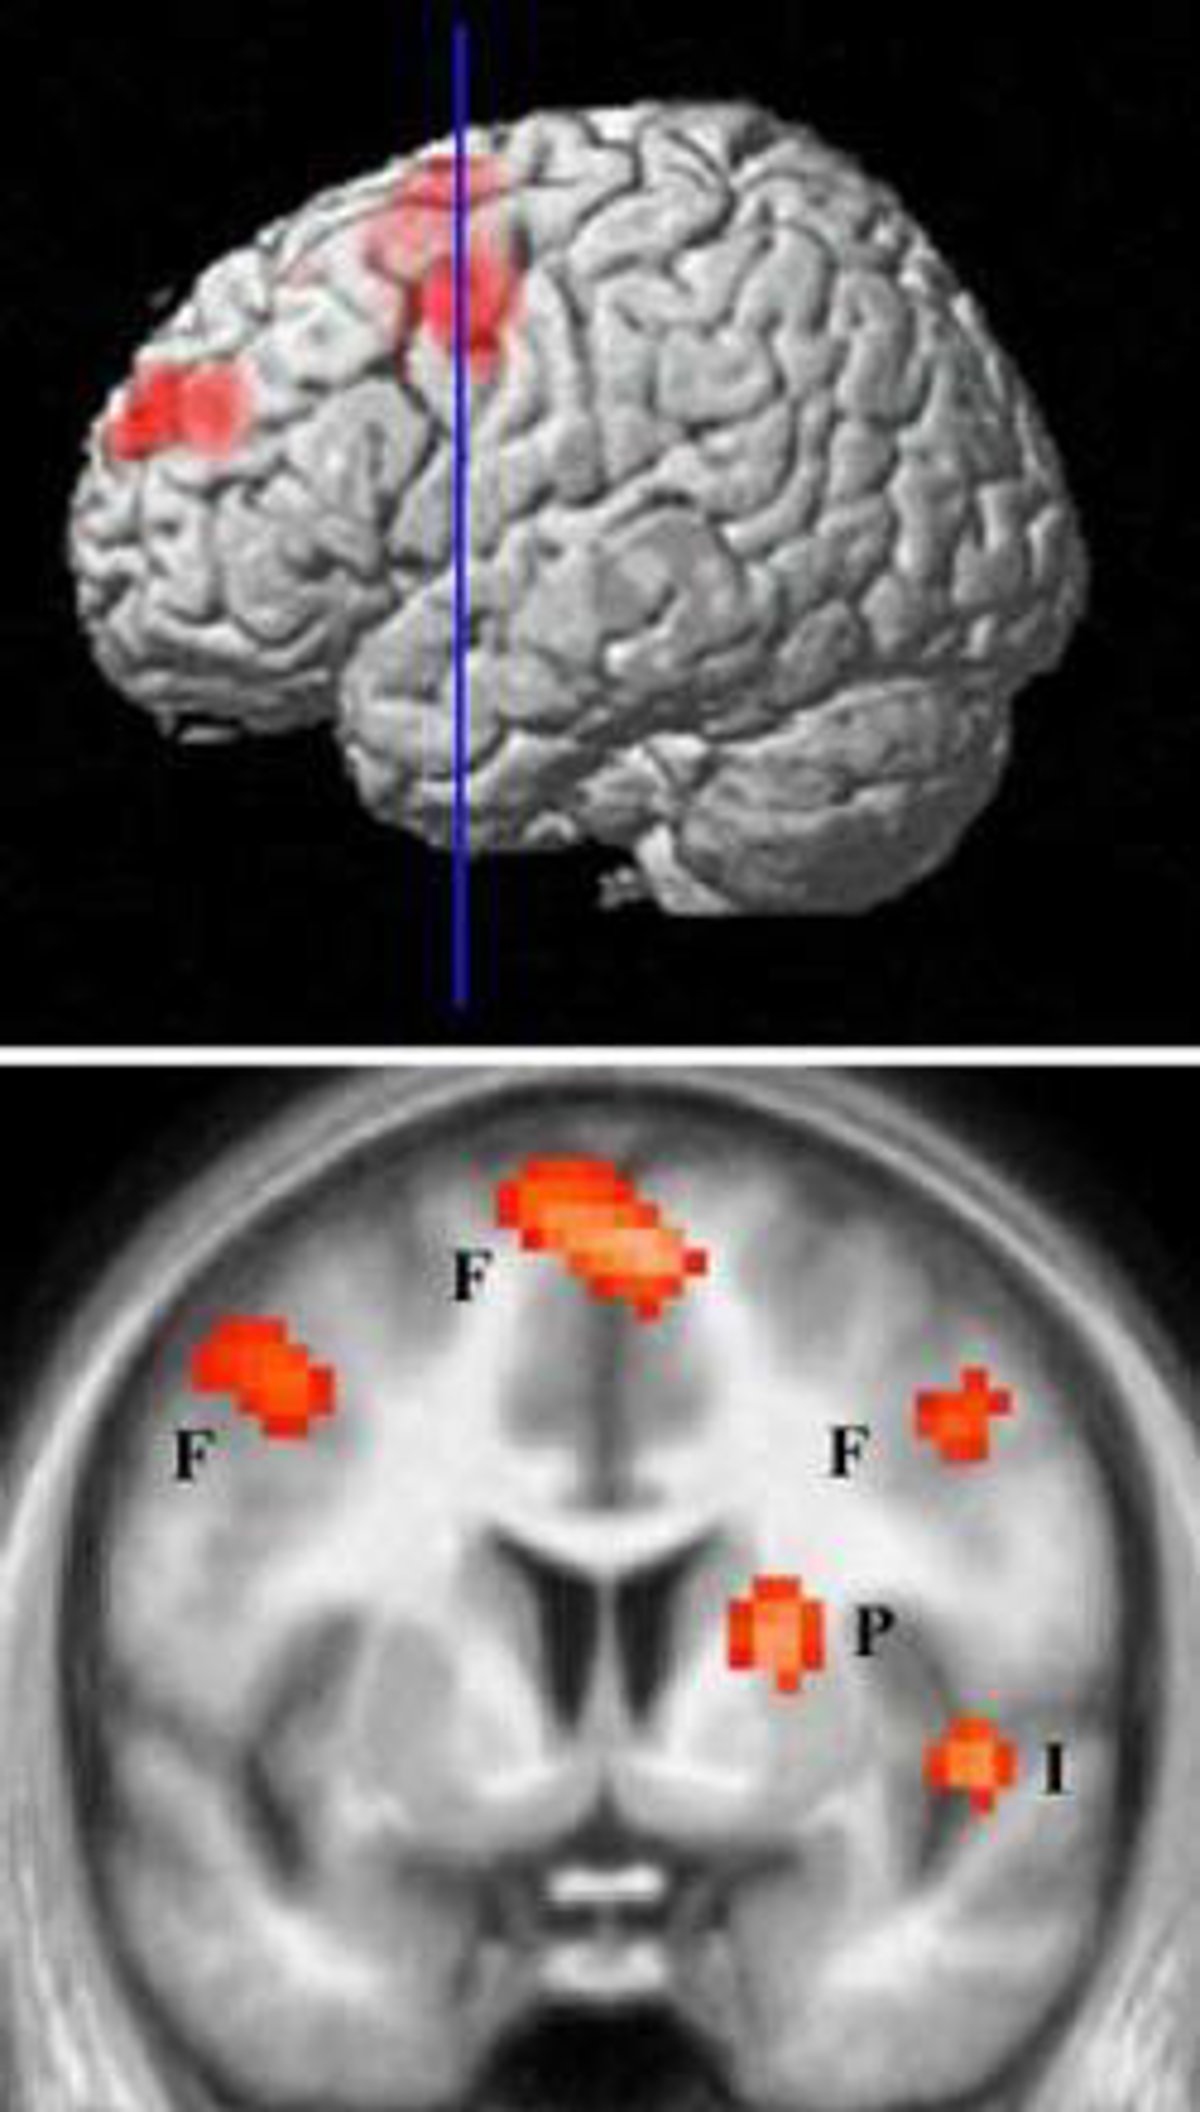

Areas cerebrales que se activan ante una persona odiada